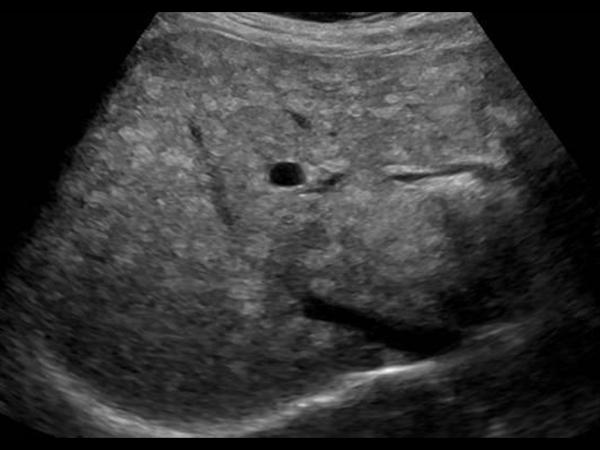

Gan nhiễm mỡ - Ảnh 2

Gan nhiễm mỡ

» Thông tin: Nữ giới – 59 tuổi.

» Lâm sàng: Kiểm tra sức khỏe.